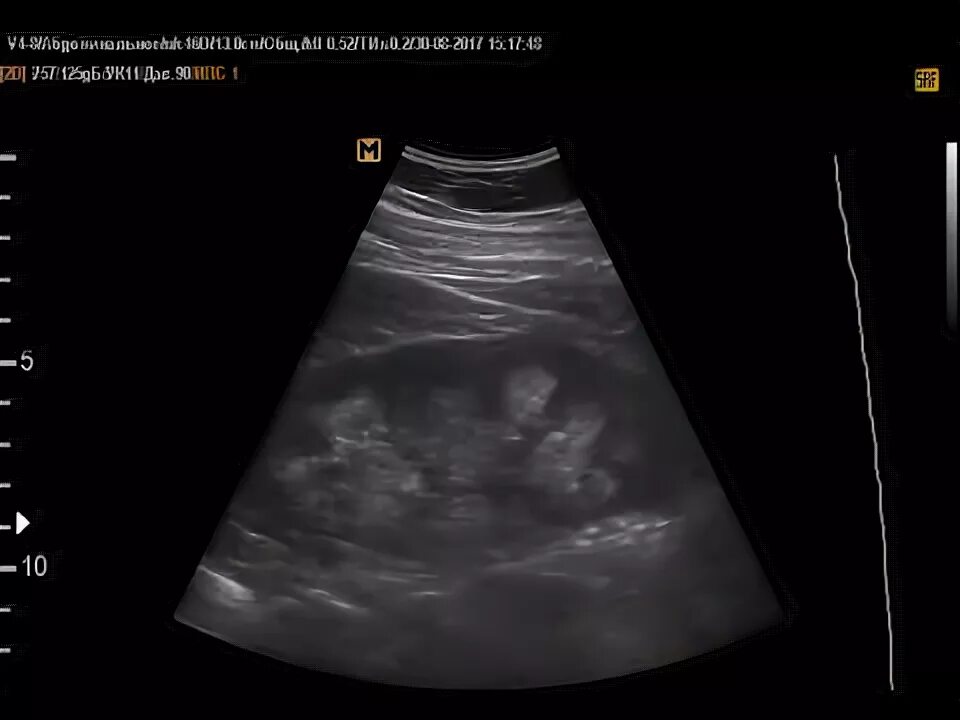

Медуллярная губчатая почка узи. синдром гиперэхогенных пирамид на узи. медуллярная дисплазия почек узи.

Синдром гиперэхогенных пирамид на узи. синдром гиперэхогенных пирамид почек узи. расширение пирамидок в почках на узи. гиперэхогенные пирамидки в почках на узи.

Синдром выделяющихся пирамид. симптом выделенных пирамид. симптом выделяющихся пирамидок. синдром перимедуллярного кольца почки что это.

Синдром гиперэхогенных пирамидок почек. синдром гиперэхогенных пирамидок на узи. синдром гиперэхогенных пирамид почек узи. гиперэхогенные пирамиды в почках на узи.

Синдром гиперэхогенных пирамид почек узи. синдром гиперэхогенных пирамидок на узи. гиперэхогенные пирамидки в почках на узи. медуллярный нефрокальциноз на узи.

Медуллярная губчатая почка узи. медуллярный нефрокальциноз почек узи. синдром гиперэхогенных пирамид почек узи.

Гиперэхогенные пирамидки в почках на узи. синдром гиперэхогенных пирамид на узи. медуллярная кистозная дисплазия почек узи. синдром гиперэхогенных пирамид почек узи.